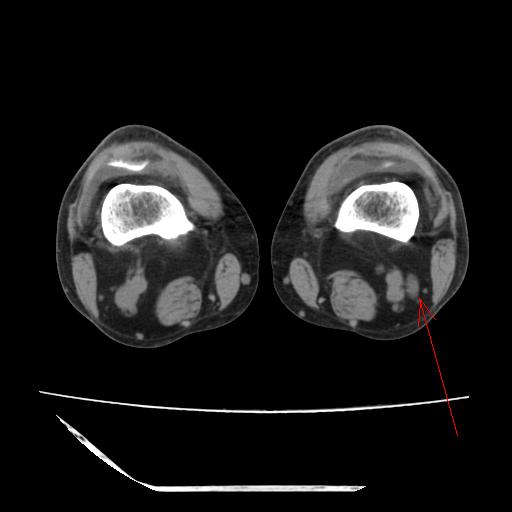

标题: CT13225:老年男性,左膝关节疼痛数月;请各位老师讨论。 [打印本页]

标题: CT13225:老年男性,左膝关节疼痛数月;请各位老师讨论。

骨质增生,骨性关节面硬化,关节积液,考虑退行性骨关节病

关节腔内少量积液,关节面退变。

双膝退变

骨质增生,骨性关节面硬化,关节间隙失常,关节积液,考虑退行性骨关节病.

骨质增生,骨性关节面硬化,关节积液,考虑退行性骨关节病。

这个病例诊断:退行性骨关节炎